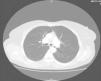

Since then, blood test have been carried out to monitor her, and on occasions imaging studies performed. During the last follow-up, blood tests were normal and gastrin levels were 717 pg/ml (VN<100) and chromogranin A was 340 ng/ml (VN 19.4–98.1). Thyroid hormones were normal. Calcium in urine for 24 hours was normal and 5-hydroxy-indoleacetic acid was 4.35 mg (VN 2.0–9.0). From 2000 to 2008, several measurements of blood gastrin were made and their values ranged from 700 to 900 pg. Thoracoabdominal tomography revealed the presence of a 5mm-diameter nodule in the left main bronchus (LMB) (fig. 1). Given this finding, a radiolabeled octreotide scintigraphy (octreoscan) was performed, which showed a focus with high uptake at the level of the mediastinum (fig. 2) coincident with the lesion observed on the CT. Bronchoscopy confirmed the existence of a clearly defined and highly vascular tumour in the LMB wall, more than 2 cm from the main carina. The bronchial biopsy and immunohistochemical studies confirmed that it was a typical carcinoid.